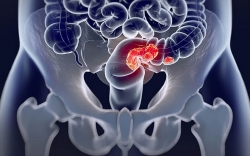

Ung thư đại tràng là gì? Nguyên nhân, triệu chứng và cách điều trị ung thư đại tràng

Ung thư đại tràng ngày càng trẻ hoá và đe dọa tính mạng của người bệnh nếu không được phát hiện sớm và điều trị kịp thời. Vậy ung thư đại tràng là gì? Nguyên ...